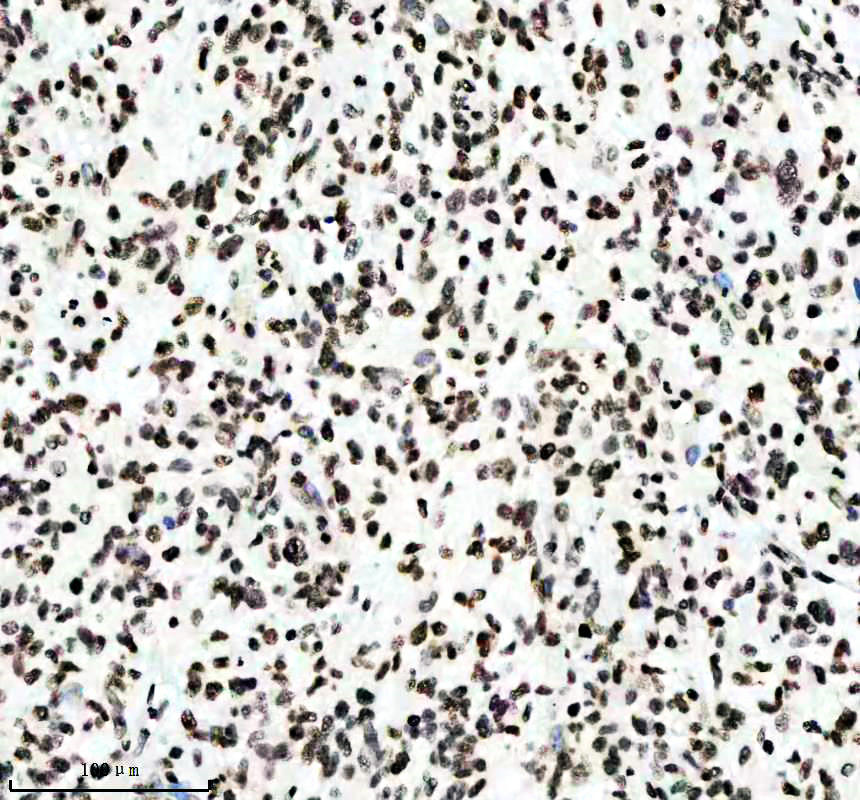

IHC analysis of Histone H3 (acetyl K14) using anti-Histone H3 (acetyl K14) antibody (BM4151) .

Histone H3 (acetyl K14) was detected in a paraffin-embedded section of human lymphoma tissue. The tissue section was incubated with rabbit anti-Histone H3 (acetyl K14) Antibody (BM4151) at a dilution of 1:200 and developed using HRP Conjugated Rabbit IgG Super Vision Assay Kit (Catalog # SV0002) with DAB (Catalog # AR1027) as the chromogen.

IHC analysis of Histone H3 (acetyl K14) using anti-Histone H3 (acetyl K14) antibody (BM4151) .

Histone H3 (acetyl K14) was detected in a paraffin-embedded section of human lymphoma tissue. The tissue section was incubated with rabbit anti-Histone H3 (acetyl K14) Antibody (BM4151) at a dilution of 1:200 and developed using HRP Conjugated Rabbit IgG Super Vision Assay Kit (Catalog # SV0002) with DAB (Catalog # AR1027) as the chromogen.